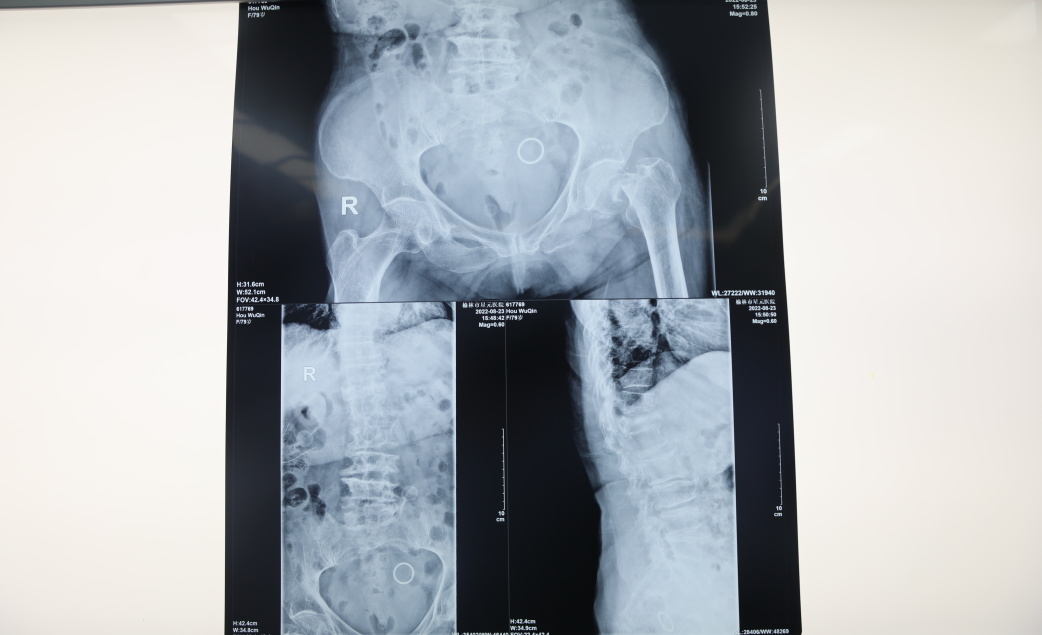

救助的患者79岁,在行走时不慎滑倒,近日疼痛加剧,到医院检查后诊断为左股骨颈骨折、腰椎骨折、骨质疏松,且患有高血压、腰椎管狭窄症、冠心病、脑梗等基础病。

在麻醉科朱光贤主任,李勇副主任医师全麻配合下,脊柱外科主任医师杨文学、主任医师乔永军、住院医师李栋等共同为患者行左股骨颈骨折人工股骨头置换术,整个手术用时30分钟,术后患者安返病房。